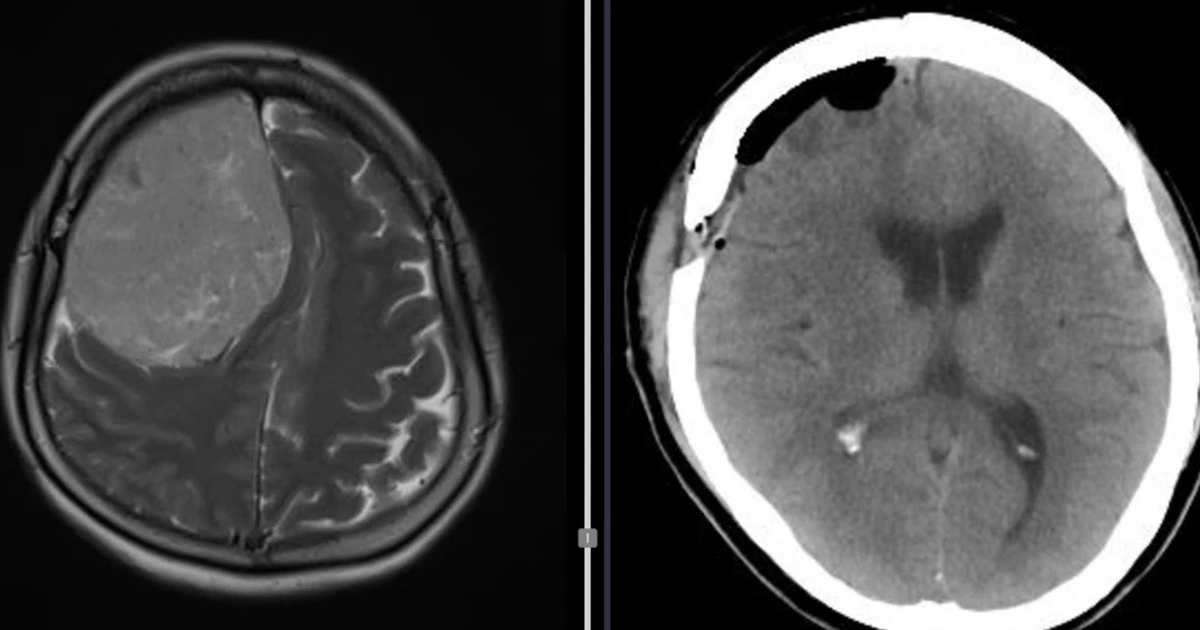

Nữ bệnh nhân ở Vĩnh Long có khối u màng não nặng 600 gram được ê kíp Bệnh viện đa khoa Trà Vinh phẫu thuật bóc tách thành công.